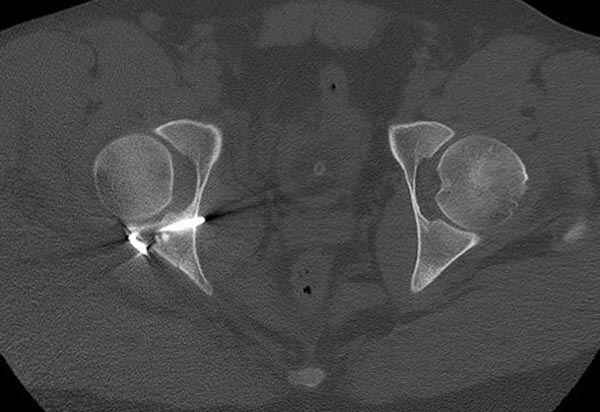

11:50 больной в послеоперационной, рентгенограмма N7, компьютерная томограмма в тот же день N8-10